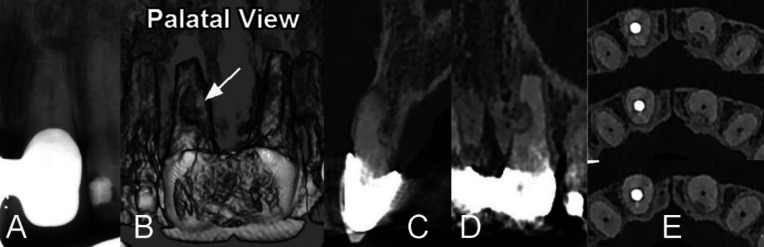

Invasive cervical root resorption (ICRR) is a dental pathology, marked by unexpected destruction originating in the cervical region of the tooth. This comprehensive literature review provides a holistic view into the pathogenesis, clinical manifestation, and precise management of ICRR, aiming to guide endodontists and enhance patient care and treatment outcomes. The review delves into the potential etiology of ICRR, covering contributing factors such as trauma, orthodontic treatment, and other pertinent conditions. It outlines the clinical and radiographic indicators, underscoring the crucial role of early detection and precise diagnosis in effectively managing and halting ICRR progression. The exploration of treatment approaches is thorough, ranging from non-surgical methods like vital pulp therapy or root canal treatment to surgical interventions. This review accentuates the essential role of interdisciplinary collaboration among diverse dental specialties in enhancing ICRR management. It highlights the importance of a consolidated strategy in enhancing treatment outcomes and preserving tooth structure and function. Moreover, it investigates prevention methods, risk evaluation, and identifies prospective research pathways to address the existing knowledge gaps.